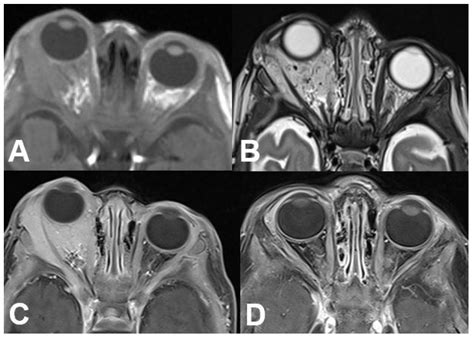

• Ocular Ultrasound: Uses sound waves to create images of the inside of the eye, helping to measure the size and shape of a tumor.

• Optical Coherence Tomography (OCT): Provides high-resolution cross-sectional images of the retina.